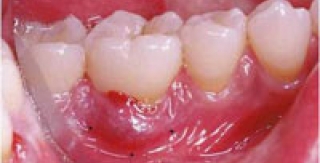

Nha chu liên quan trực tiếp đến mô nâng đỡ quanh chân răng, bao gồm bệnh của nướu và các bệnh lý phá hủy mô nâng đỡ sâu bên dưới nướu (xương ổ răng, dây chằng nha chu...). Nha chu là nguyên nhân quan trọng gây mất răng. Phòng ngừa bệnh nha chu Bệnh thường diễn biến qua 2 giai đoạn: viêm nướu và viêm nha chu. Nếu nướu bị viêm, ta sẽ thấy một hoặc nhiều dấu hiệu sau: - Nướu đổi màu so với...

Tụt lợi là quá trình lộ bề mặt chân răng do sự di chuyển về phía chóp chân răng của lợi. Tụt lợi là điềm báo trước sự mất cement chân răng, lộ ngà, tăng cảm giác và giảm thẩm mỹ. Phương pháp điều trị tụt lợi tốt nhất là ghép nha chu chân răng.